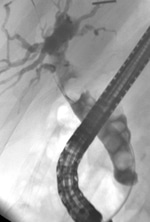

A large bile duct stone is impacted at the major duodenal papilla causing obstruction and severe infection of the bile duct. In this case, ERCP is urgently required to relieve the obstruction.